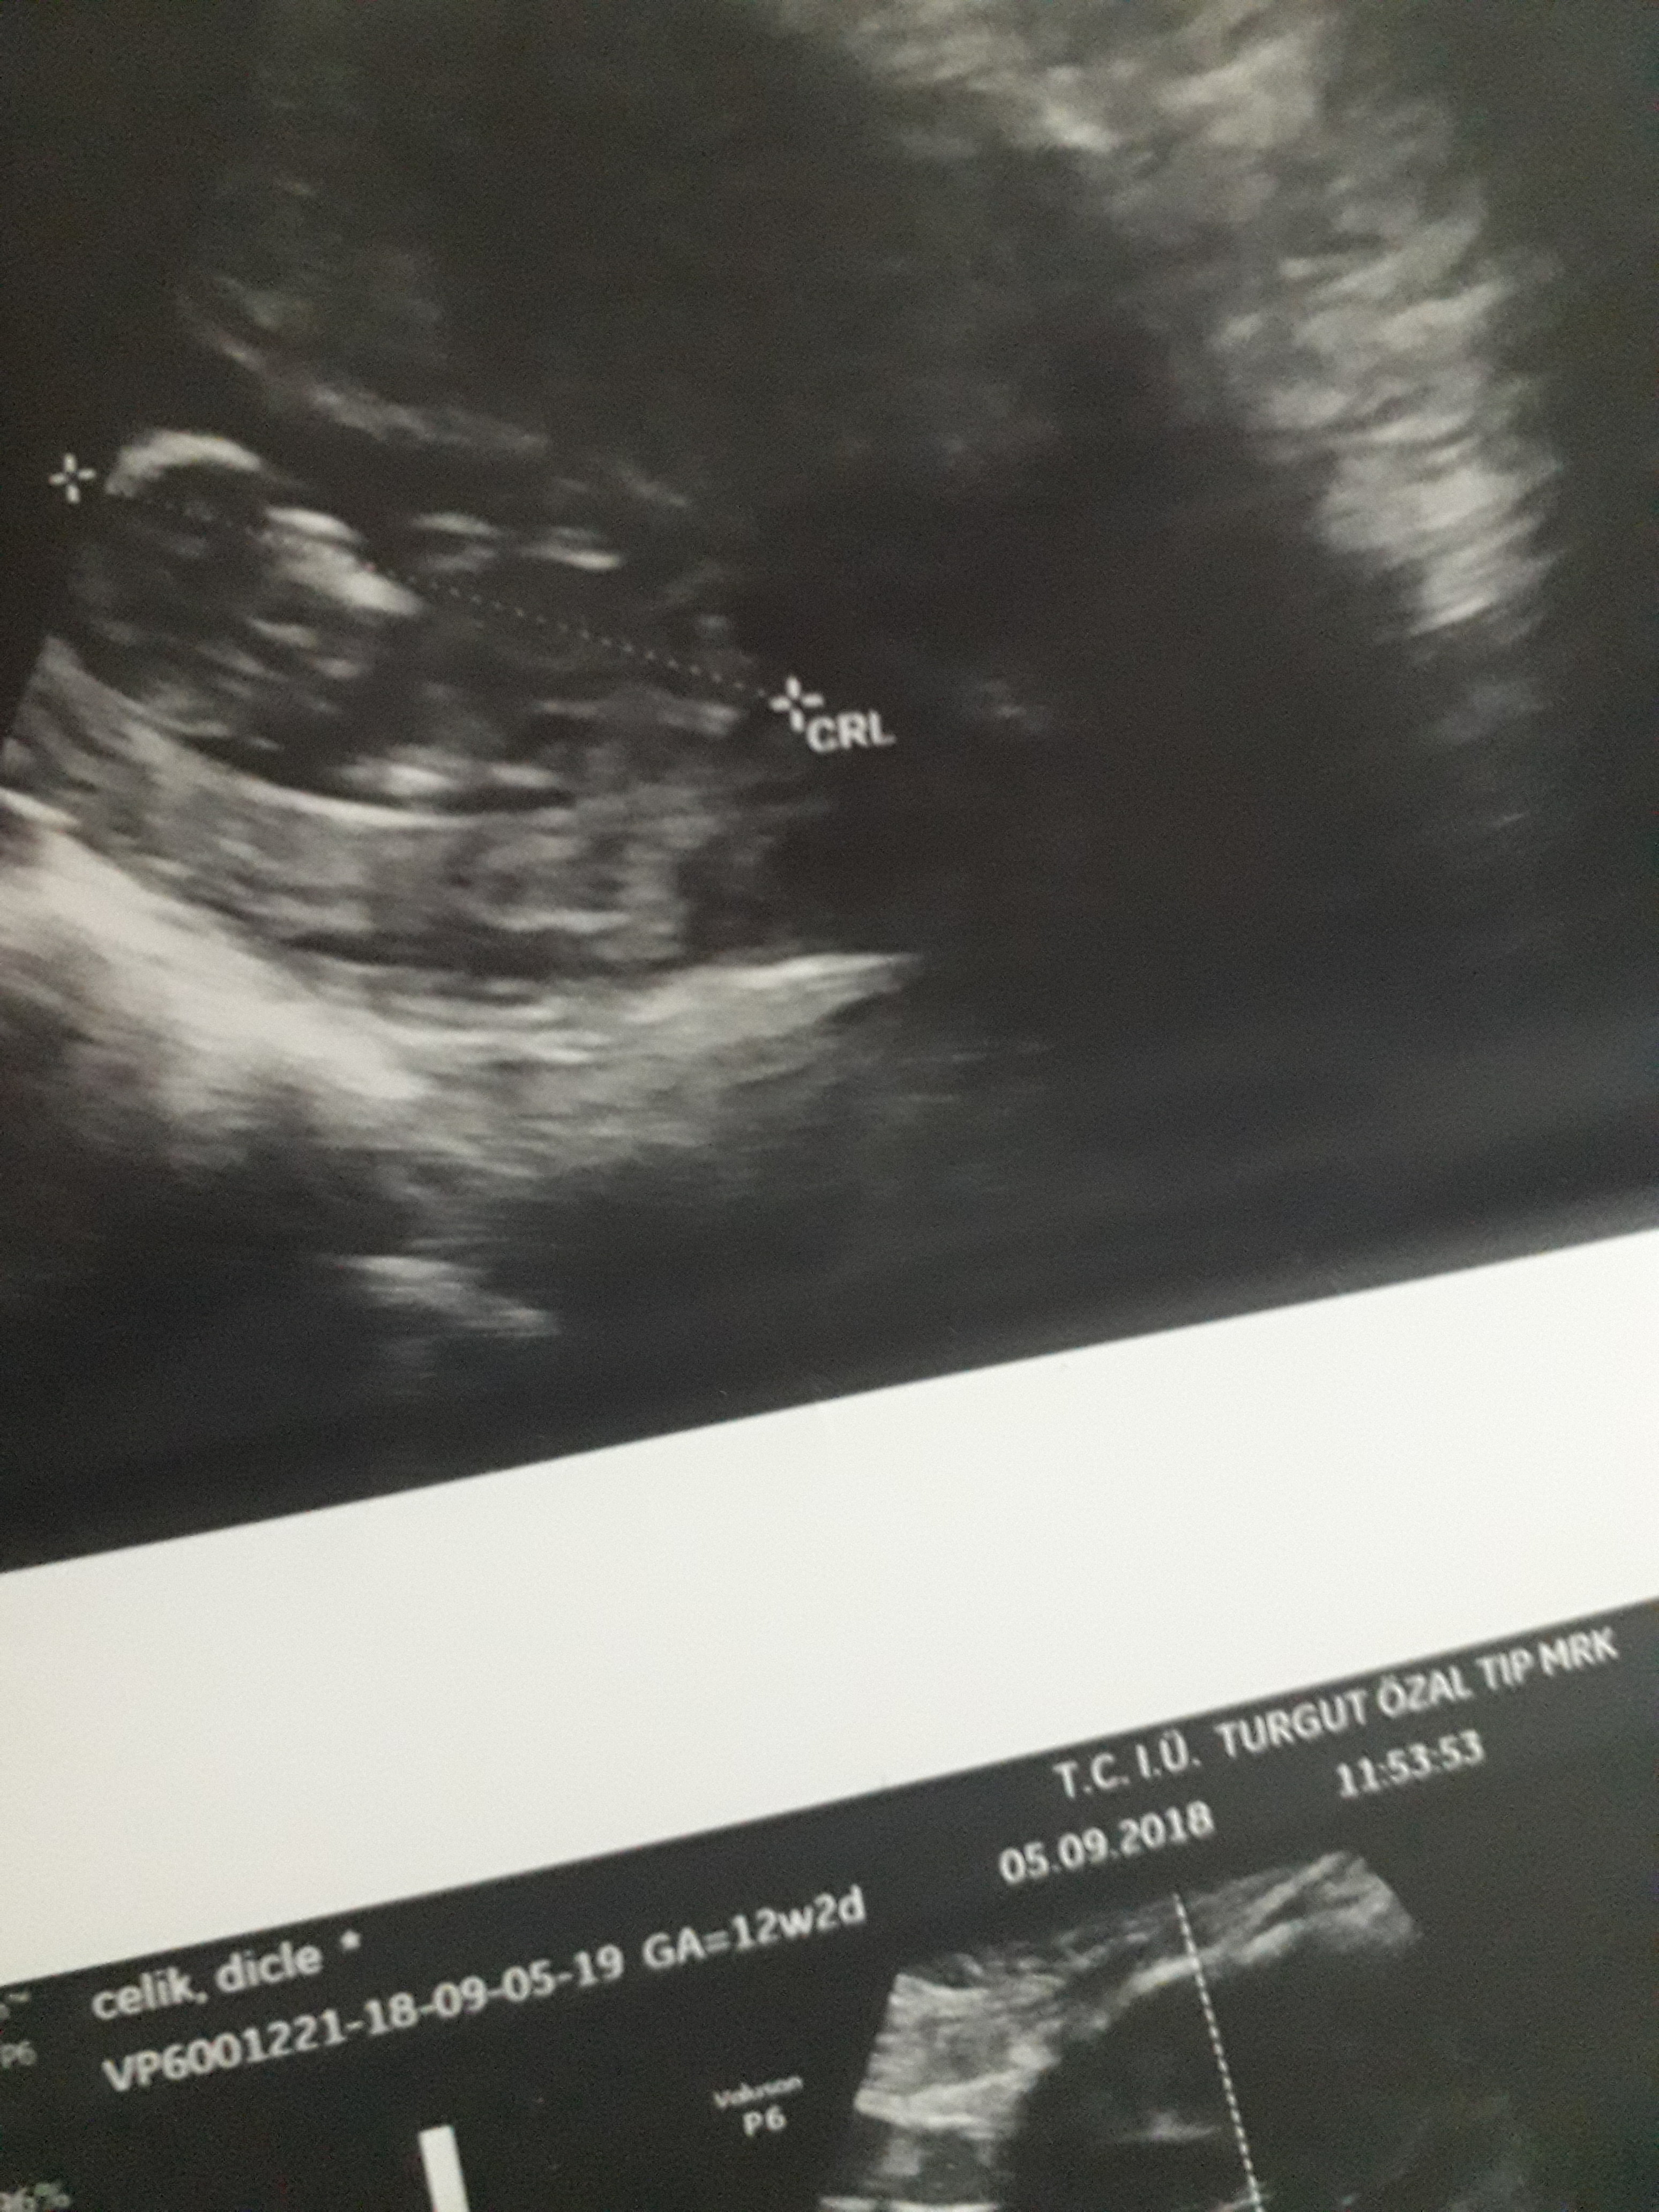

Dun malatyada verildi 12 +4 gunluk lutfen yorumlayin

Dun verildi 12 haftalik lutfen yorumlayin

Görsellerde nub çıkıntısı belli değil . Ultrasonu yapan doktor cinsiyeti hakkında bilgi vermiştir mutlaka ama şunu belirtmeden geçmeyeyim. Bu haftalarda cinsiyet tahmininde yanılma payı çok yüksek 17-19 ve 20 ci haftalarda bebeğin cinsiyetini net olarak öğrenebilirsiniz.